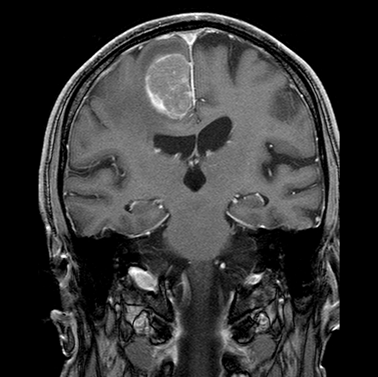

MRI provides even more definitive proof. On T1 weighed images they are usually hypointense, on T2 weighed images their signal is strong. Although these signs are very characteristic, normally they are still insufficient for exact differential diagnostic criteria.

MRI has the greatest sensitivity in the detection of neoplastic brain lesions. The relaxation time of tumor is usually longer than that of the surrounding normal tissues. Therefore on T1W images neoplasms have slightly weaker signal intensity, while on T2W images they are more hyperintense than normal parenchyma. This signal pattern can be very characteristic and has great diagnostic value. However, secondary neoplastic signs, such as mass-effect of the tumor cannot be neglect either. A space occupying lesion can cause:

Most often its symptoms present poorly and disease progression is long. It is the most common intracranial tumor, but it is typically benign. Its complications are determined by the localization and the size of the tumor.

Meningiomas are often (but not always) surrounded by sharp edged swelling and perifocal edema. They might appear isodense compared to brain parenchyma on CT. They often contain sclerotic parts and usually they show an increased enhancement of iodinated contrast media.

MRI: Meningiomas show a good Gadolinium enhancement with a characteristic “dural tail” sign (a thickening in the neighboring dura).

Small metastases can produce very extensive edemas. Multiplicity is common. Due to the consequential blood-brain barrier disorders their contrast enhancement is very intense.